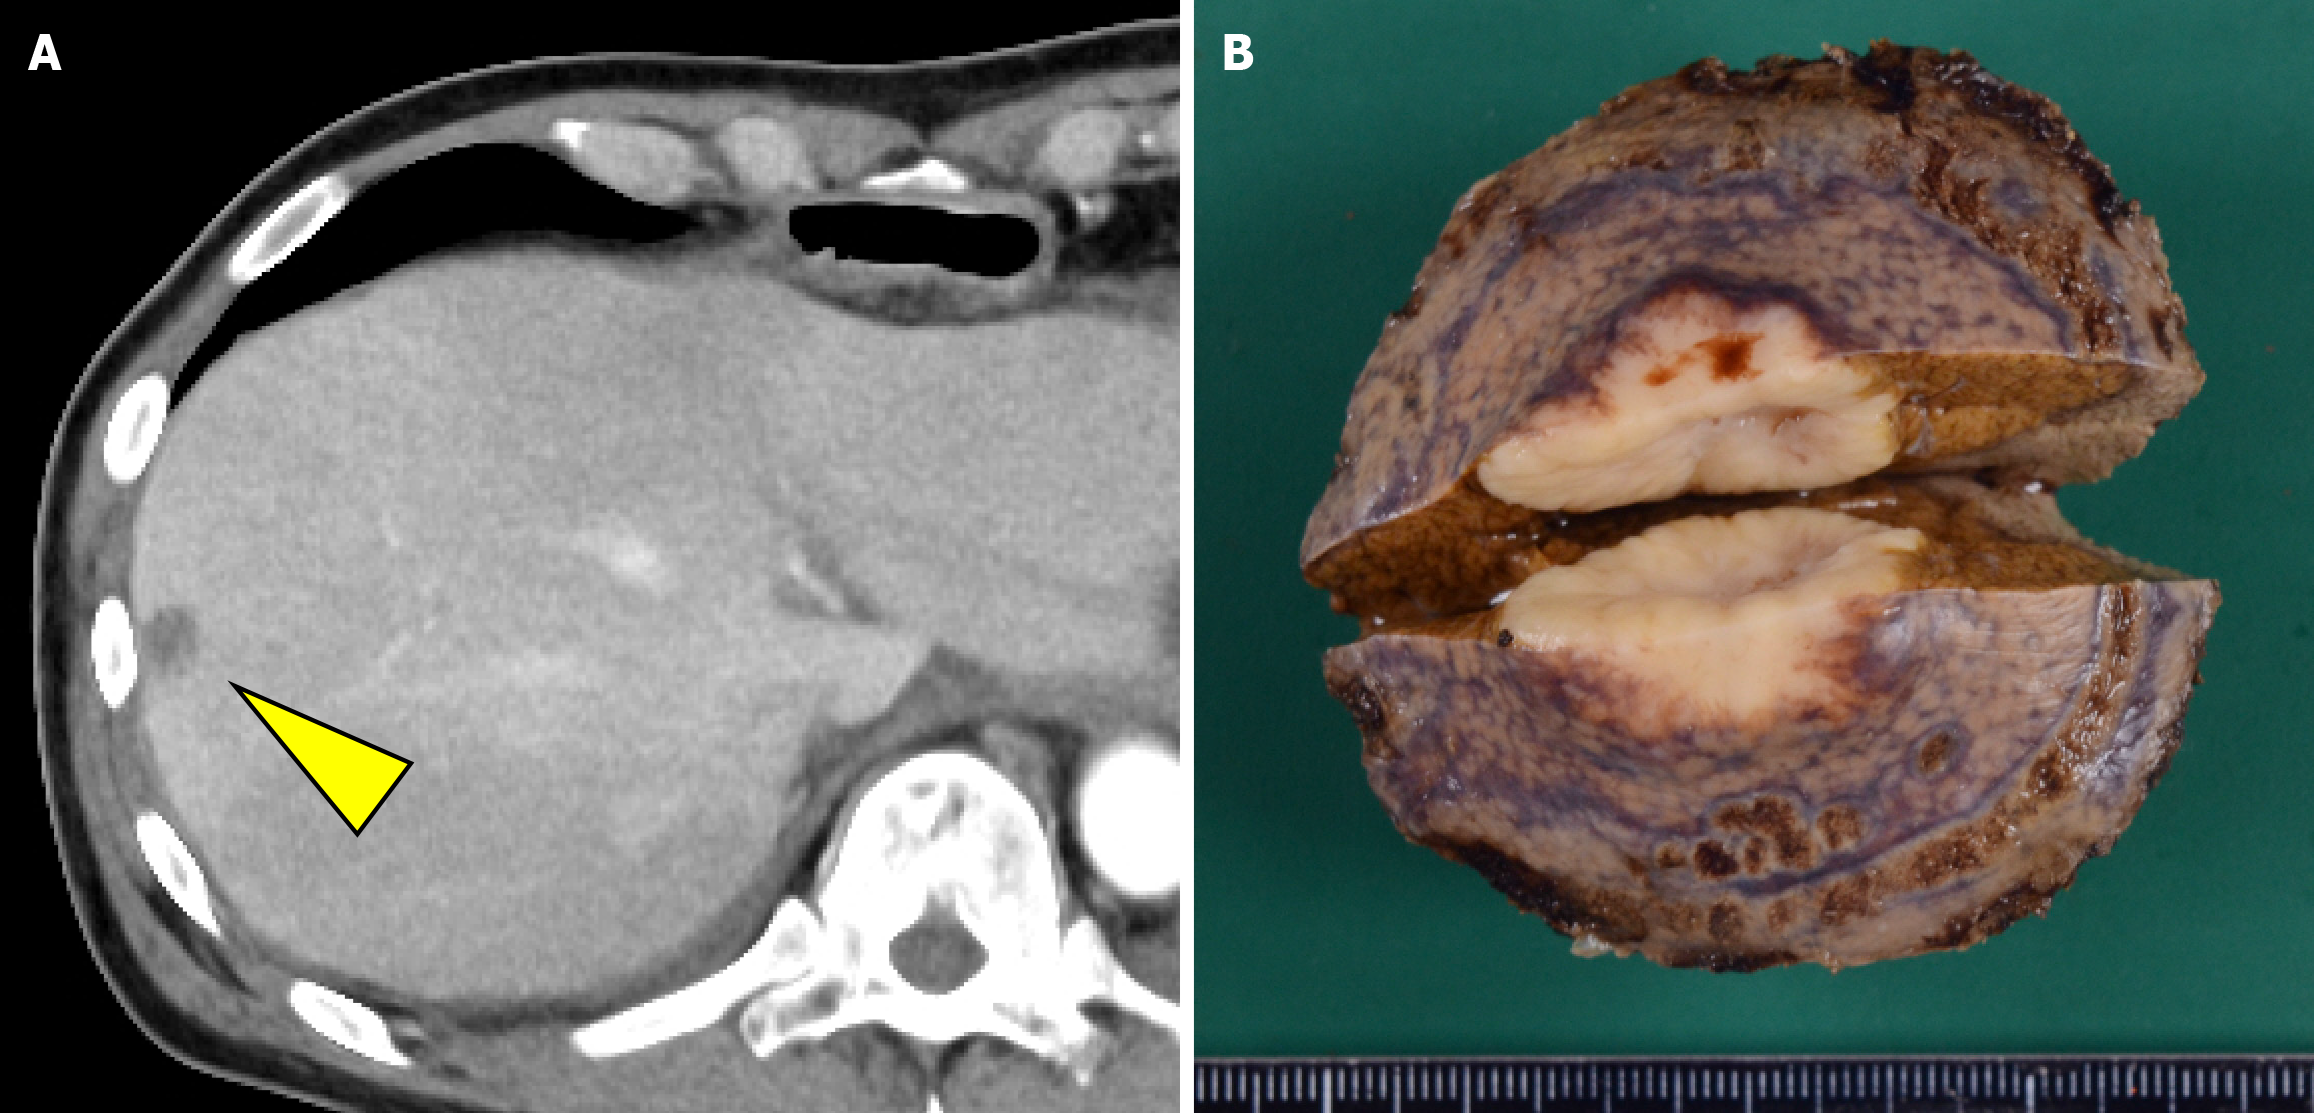

The patient resumed oral intake on postoperative day 7 and was discharged from the hospital on postoperative day 20. However, CT performed within 1 month postoperatively revealed a hypovascular nodule in liver segment 8 that was undetectable preoperatively (Figure 6). Metastatic hepatocellular carcinoma was suspected. Given that the histopathological findings of the primary lesion and metastatic lymph nodes were consistent with only NEC, four courses of irinotecan + cisplatin (IP) chemotherapy (IP: Irinotecan 60 mg/m²/day on days 1, 8, and 15 and cisplatin 60 mg/m²/day on day 1) were administered, and the cisplatin dose was reduced to 75% starting from the third course because of renal function decline. Despite treatment, the lesion increased in size from 15 mm to approximately 23 mm and was classified as progressive disease. After a multidisciplinary discussion, surgical treatment was planned, and partial segment 8 resection was performed. There were adhesions in the abdominal cavity because of the previous surgery, and the Pringle maneuver was not used. Histopathological examination confirmed metastasis of esophageal NEC. Subsequently, based on the efficacy of IP therapy, six courses of amrubicin (40 mg/m² on days 1-3) were administered as a second-line treatment.